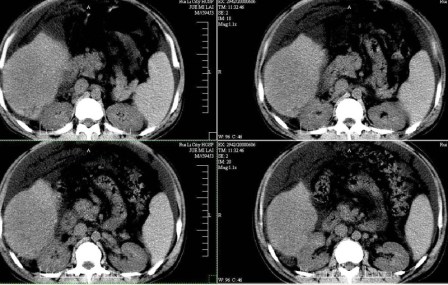

标题: CT13930:M,33岁,腹胀、腹痛10天余。 [打印本页]

标题: CT13930:M,33岁,腹胀、腹痛10天余。

右上腹压痛,肝大,质硬。腹水征。ct:肝右叶(后段)低密度影,性质待定。

肝右叶肝癌,左叶肝内转移可能,肝硬化

肝硬化、腹水,肝右叶低密度首先考虑肝癌可能,左叶低密度不除外转移可能。建议增强检查。

肝硬化、大量腹水,肝右叶巨大肿块,境界欠清,中间见不规则低密度坏死区,考虑肝癌应该问题不大,至于肝左叶低密度灶是否转移应该意义不是很大了,慎重起见还是建议增强扫描。